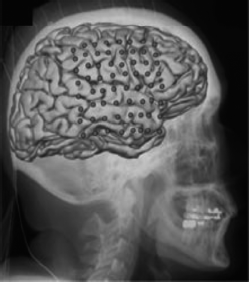

[9] The new technique involves training algorithms to recognize specific brain

[10] signals picked up by an array of nonpenetrating electrodes placed over the

[11] language centers of the brain, says Spencer Kellis, one of the bioengineers

[22] Working with colleagues Bradley Greger and Paul House, Kellis placed 16 electrodes on the surface of the brain of a

[23] patient being treated for epilepsy. The electrodes recorded signals from the facial motor cortex—an area of the brain

[24] that controls face muscles during speech—and over the Wernicke’s area, part of the cerebral cortex that is linked with

[25] language. To train the algorithm, signals were analyzed as the patient was asked to repeatedly utter the 10 words.

[26] It’s possible to use less invasive techniques, such as electroencephalography (EEG), which places electrodes _____